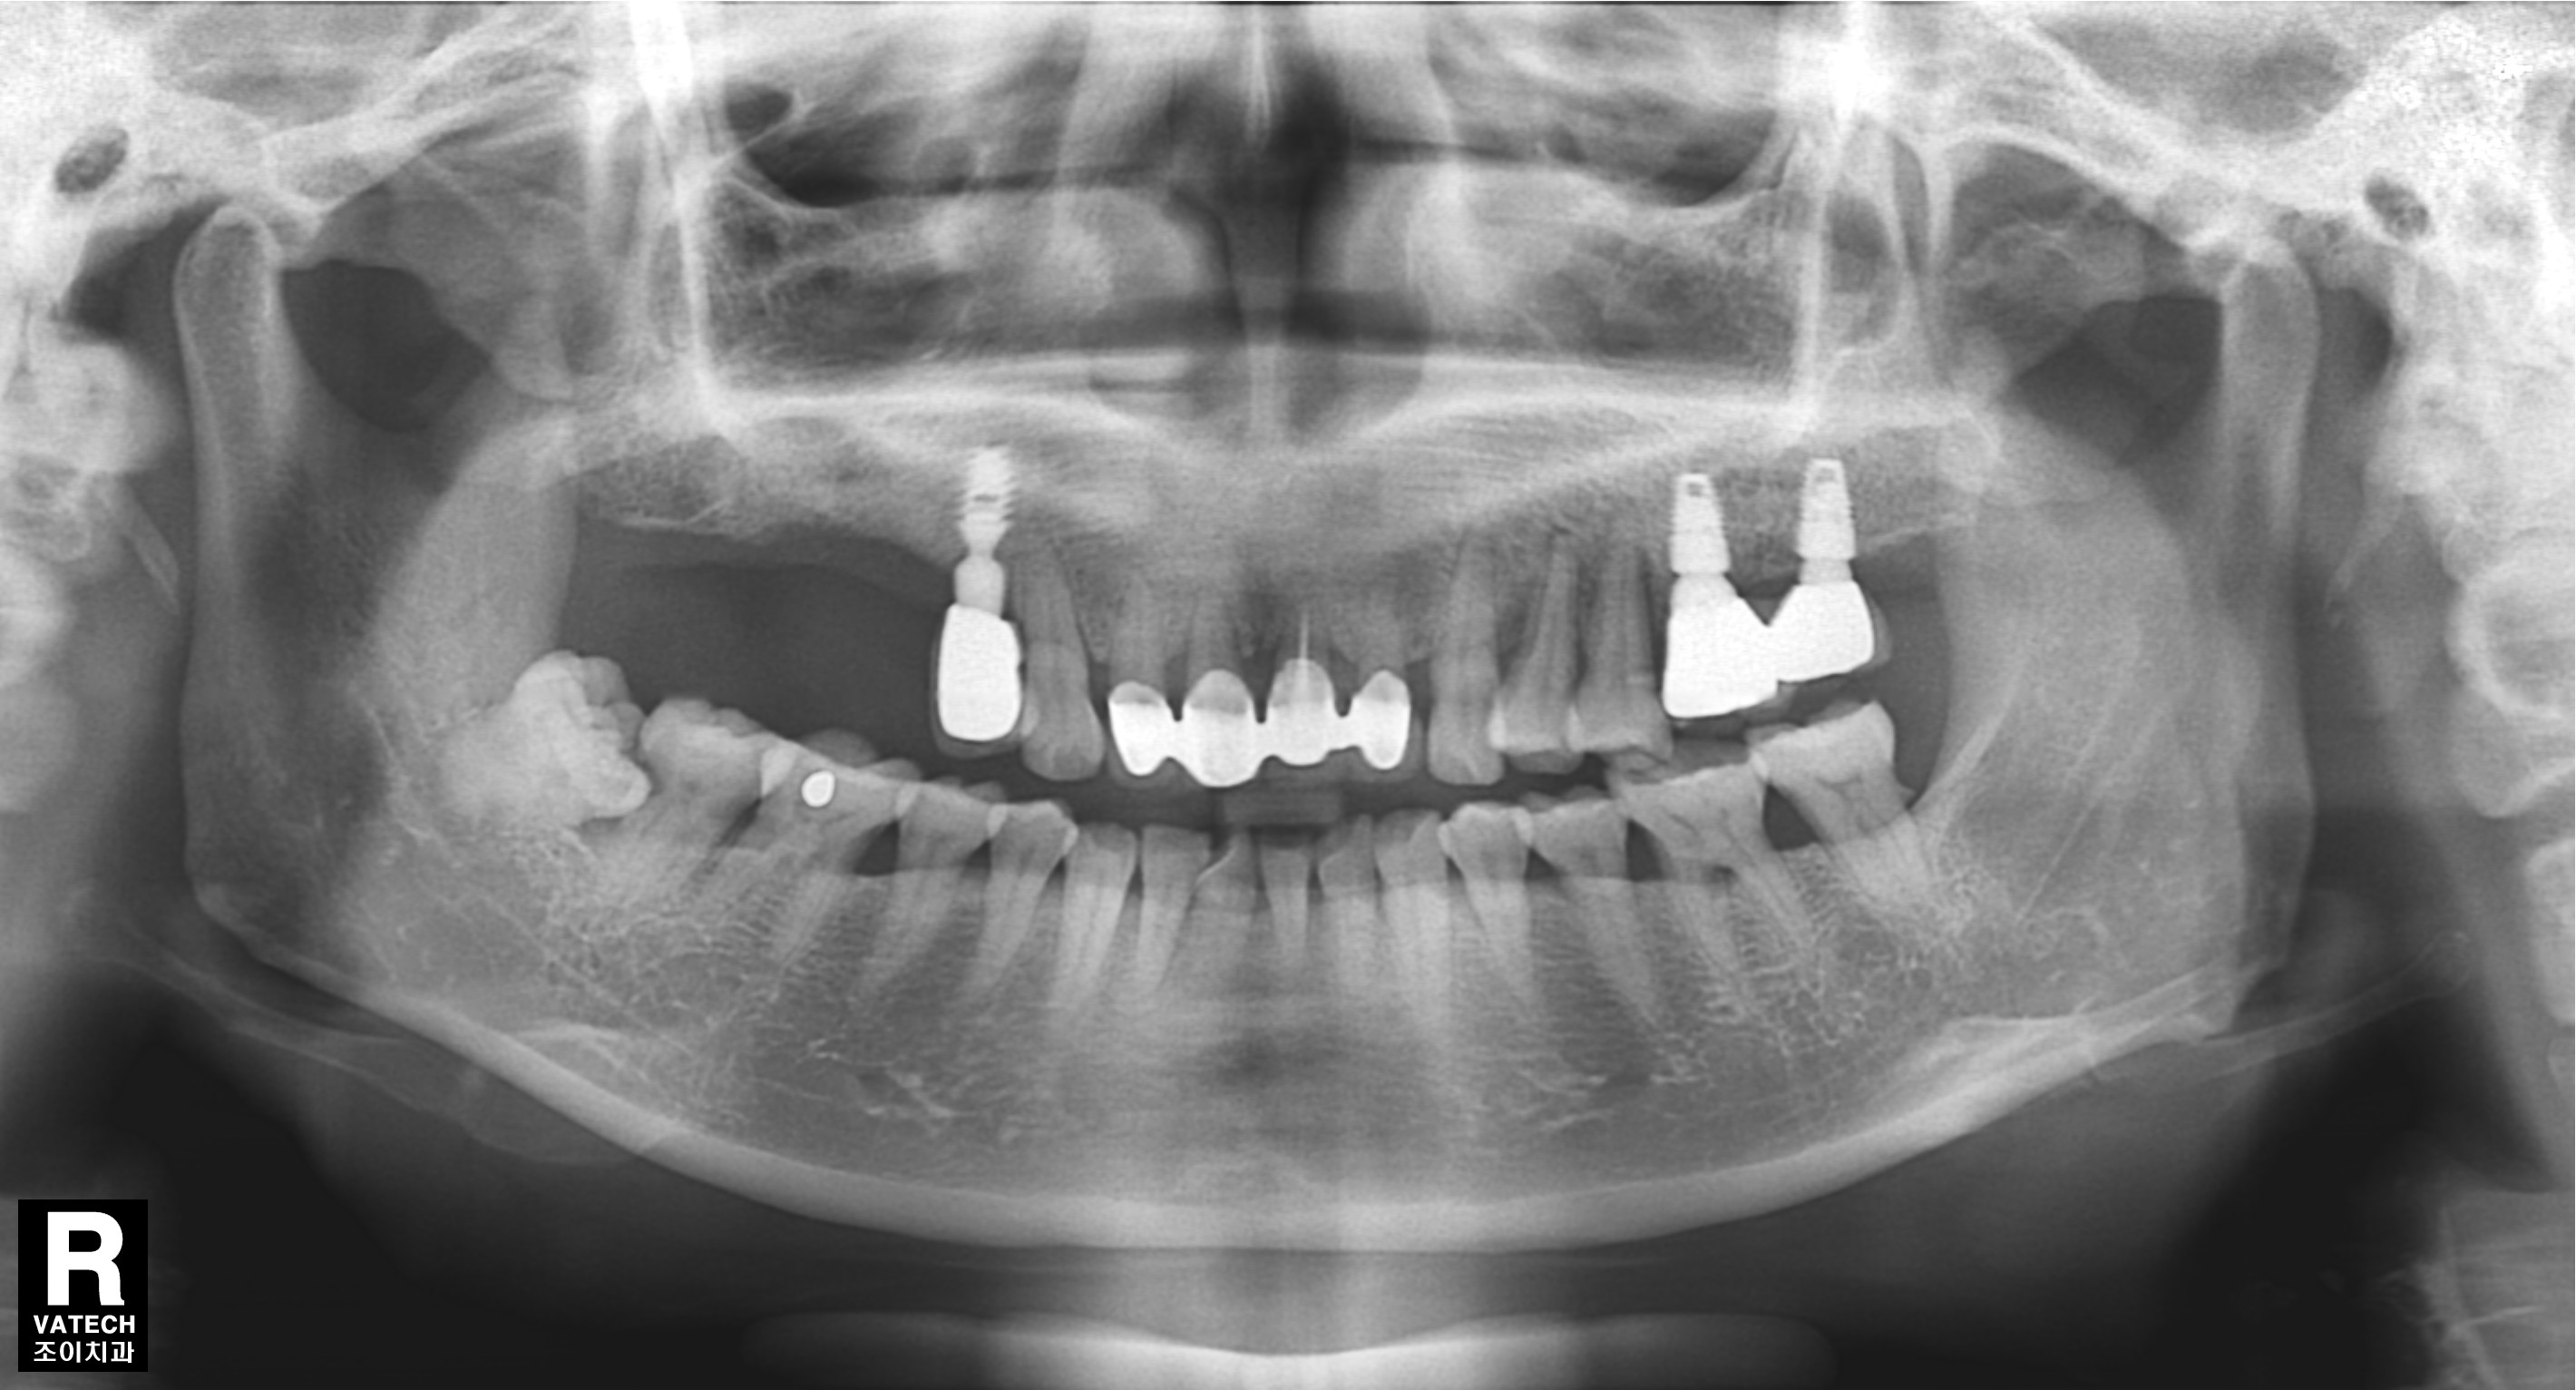

#15.16 부위로 타병원에서 수차례 실패했던 임플란트의 치료사례입니다.

임플란트 제거, 염증제거,티탄메쉬 골이식(bone graft), 서두르지 않고 충분한 경과관찰.

기본에 충실하게 step by step으로 다시 치료하는 것이 관건입니다.